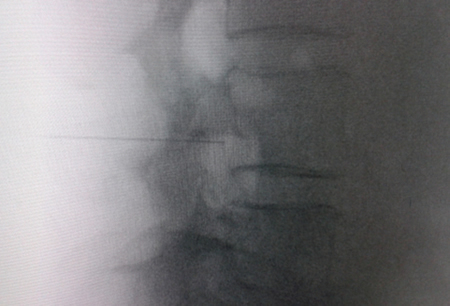

El acceso por vía transforaminal es el más utilizado (4). Se coloca al paciente en decúbito prono con una almohada a nivel abdominal para revertir la lordosis fisiológica. Las agujas o cánulas de radiofrecuencia que utilizamos con más frecuencia son de diámetro 20 o 22 G de 98 mm de largo con punta activa de 0,5 o 1 cm. Después de la asepsia con clorhexidina alcohólica y la colocación de campos estériles, se realizan enfoques radiológicos en incidencia anteroposterior, oblicuo y lateral. En incidencia anteroposterior y moviendo el arco en dirección cráneo caudal se borra el doble arco del borde inferior vertebral. En incidencia oblicua entre 20 y 30 grados ipsilateral al GRD a tratar, se visualizará la clásica imagen descrita como de “Scotty Dog”, que es resultado de acercar el macizo facetario y la apófisis espinosa al lado contralateral. El punto de entrada será entonces inmediatamente debajo del pedículo. Previa anestesia local con lidocaína al 1 %, la aguja se introducirá siguiendo una visión túnel y no se avanzará más allá de la mitad del pedículo en esta proyección con la finalidad de prevenir la lesión neural. En proyección lateral, se introducirá en el techo del neuroforamen

(Figuras 1 y 2) pero la localización final será determinada por la estimulación nerviosa sensitivo-motora. La estimulación sensitiva consiste en provocar parestesia o dolor en el territorio afectado con una estimulación entre 0,3-0,6 v. Durante la estimulación motora se pueden provocar fasciculaciones en el territorio afectado con un voltaje del doble al necesario para provocar las parestesias. Si se desea realizar una denervación intraganglionar, promulgada por algunos autores, la estimulación tanto sensorial como motora será positiva a menos de 0,3 v. Por tratarse de un procedimiento más doloroso, se aconseja administrar anestésicos locales después del estímulo doloroso y antes de realizar el tratamiento. La impedancia deberá mantenerse por debajo de 450 ohms, lo que se consigue infundiendo solución salina previa a la RF (4). La utilización de contraste constituye una buena práctica, ya que descarta la posición intravascular e intratecal de la cánula de radiofrecuencia.

Fig. 1. Vista radiológica de perfil que muestra una cánula de radiofrecuencia en el ángulo anterosuperior o techo del neuroforamen, topografía aproximada del ganglio de la raíz dorsal